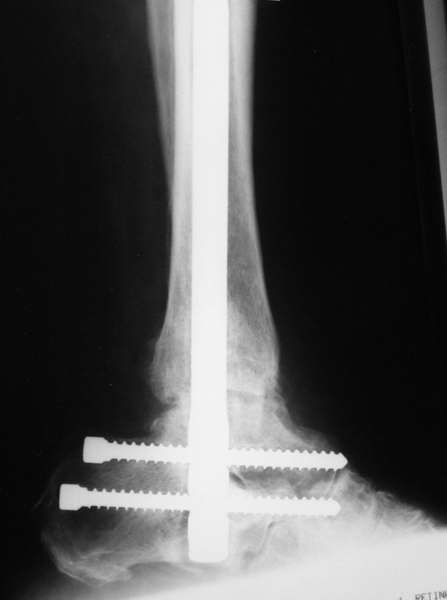

Можно: 65-летняя пациентка, оперирована по поводу несросшегося в гипсе перелома лодыжек с патологической вальгусной установкой стопы и выраженным нарушением опрной функции. Оперирована через 6 месяцев после травмы. Рентгенограммы через 4 месяца после операции.

Само формирование и рассверливание канала для штифта и есть те "отдельные мероприятия", которых достаточно...

Уважаемый А.Семенистый. Складывается впечатление, что вы выполнили трехсуставный артродез, уж больно длинные блокирующие винты. Не мешают ли они пациентке при ходьбе?

Да конечно винты длинноваты! Мешают ли ходить? Во всяком случае субьективно пациентка удовлетворена. Ходит, естевственно, хуже чеи до травмы, но намного лучше, чем до операции.